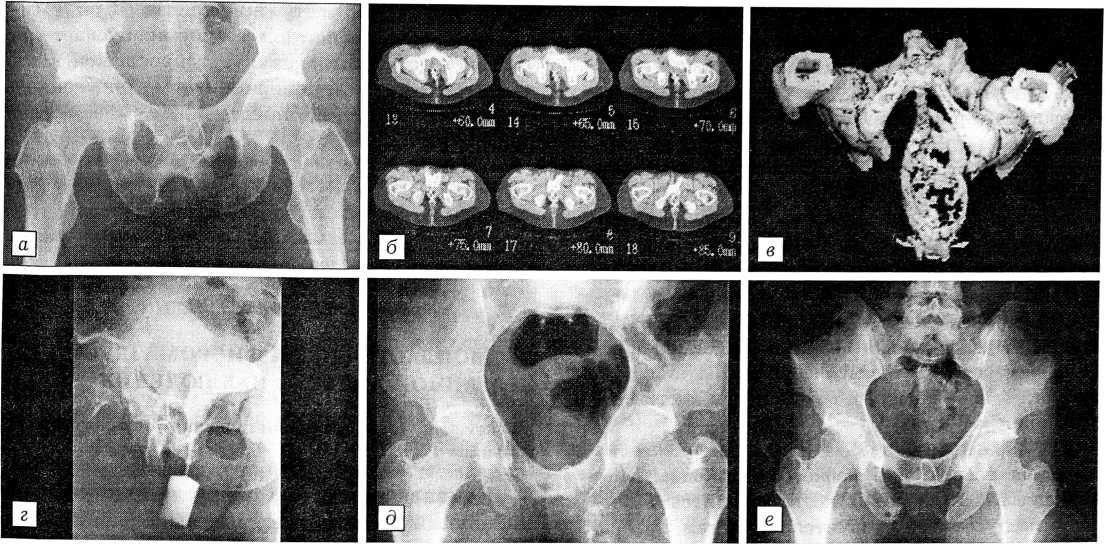

Больная С. со стабильной посттравматической деформацией тазового кольца.

а — обзорная переднезадняя рентгенограмма таза до операции: равномерносуженный цилиндрический таз (по мужскому типу), патологический синостоз лобковых костей, угол схождения нисходящих ветвей лобковых костей к симфизу 60°;

б — компьютерная томограмма таза: синостоз нисходящих ветвей лобковых костей, остеофиты по передней поверхности симфиза на широком основании;

в — компьютерная томограмма таза с дополнительным контрастированием прямой кишки, трехмерная реконструкция: сращение лобковых костей, массивные остеофиты в области анкилоза;

г — контрастное исследование уретры и мочевого пузыря.

д — обзорная переднезадняя рентгенограмма таза после операции (резекция нисходящих ветвей лобковых и седалищных костей, иссечение остеофитов);

е — обзорная переднезадняя рентгенограмма таза через 5 лет после операции: новых разрастаний в области операции нет.